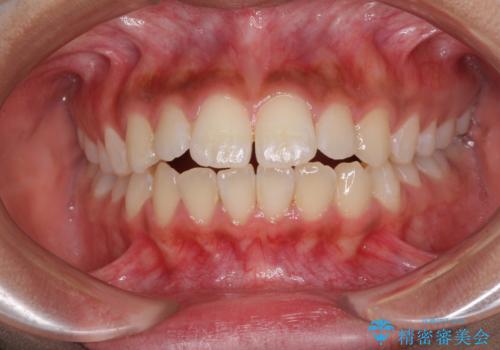

開咬をワイヤー装置で矯正治療

担当医 藤巻太一朗